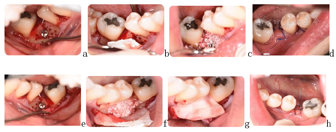

恒牙列,36、46缺失,缺隙处牙槽骨吸收、狭窄成刃状,宽度约5 mm,37、47近中倾斜;16、26、37、47咬合面银汞充填体24、34牙颈部树脂充填体;18、28、38、48正位萌出;中线正,微笑时口角偏斜;全口牙龈红肿、退缩2~3 mm;下颌双侧第一磨牙缺失,以双侧第二磨牙的关系进行安氏诊断为Ⅲ类完全近中关系,尖牙关系中性,覆

覆盖基本正常,下前牙直立,上前牙略唇倾,上下牙列轻度拥挤,Spee曲5 mm。(图1)

2).上颌粘接0.022英寸(1英寸=2.54 cm)陶瓷自锁直丝弓矫治器(Clippy,TOMY,Japan),16、26粘接直丝弓颊面管。初始弓丝为0.014英寸,依次应用0.016英寸、0.016英寸×0.022英寸、0.018英寸×0.025英寸镍钛方丝初步排齐整平上下牙列。

3).第3个月牙周科行36、46区域骨增量手术:术区翻全厚瓣后,颊侧种植机球钻打孔穿透骨皮质、按照骨增量方向打入钛钉1.5 mm×10 mm(中邦,西安,中国),植入人工骨粉(Bio-Oss,Geistlich,瑞士),高度平齐牙槽嵴顶或高于0.5 mm,宽度与第二磨牙颊舌向宽度基本一致,之后覆盖生物膜(Bio-Guide,Geistlich,瑞士),骨膜松弛切口,龈瓣冠向复位,严密缝合。术后6周开始粘下颌托槽及37、47颊面管,初始弓丝为0.014英寸。第9个月更换至上颌0.018英寸×0.025英寸、下颌0.017英寸×0.025英寸不锈钢方丝,滑动法内收前牙、近中移动并直立37、47。治疗过程中37、38出现舌倾,配合局部方丝弓正转矩控制(图2)。

4).第13个月下颌缺牙间隙基本关闭,逐步粘结38、48带环进一步排齐关闭剩余间隙。第25个月下颌更换0.018英寸×0.025英寸不锈钢方丝进一步直立第二三磨牙(图3)。